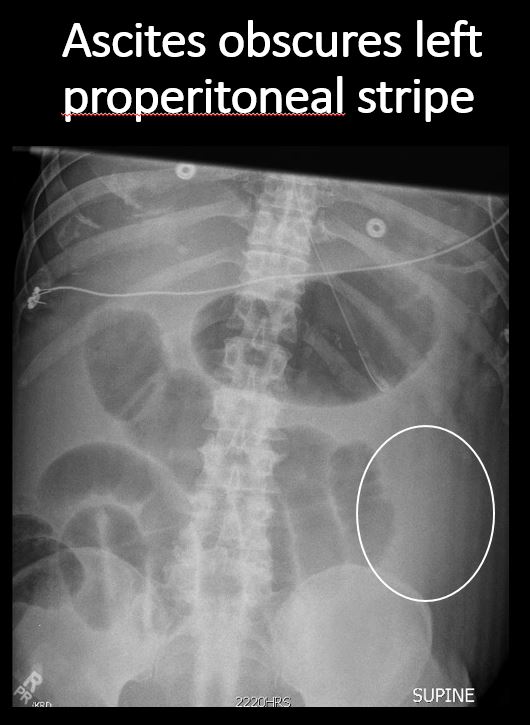

The right or left properitoneal stripe is obscured. [Yes/No]